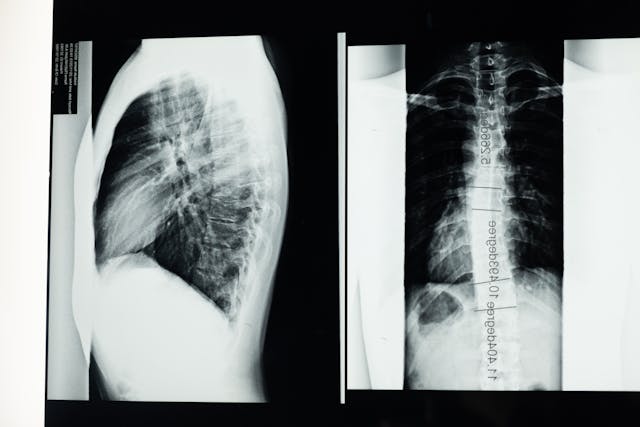

Existuje spousta nemocí, které mohou člověku pořádně znepříjemnit život. A rozhodně nejde jen o nemoci, které se objevují v rámci sezony respiračních onemocnění. Velká část nemocí postihuje pohybový aparát, což je například skolióza. Je to nemoc páteře, která postihuje obratle. Páteř je křivá na jednom nebo více místech a kvůli tomu má pacient, který jí trpí, neustálé bolesti. Skolióza se může objevit v krční, hrudní i bederní páteři. Může být mírná, ale mnozí pacienti mají skoliózu natolik výraznou, že se projeví i na jejich vzhledu. Často tito lidé mají třeba křivá záda na první pohled, jedno rameno výš než druhé anebo třeba hrb.

Není to jen estetický problém, který také není radno podceňovat, protože tím samozřejmě utrpí i sebevědomí člověka a tím i jeho psychika. Závažné skoliózy se řeší operací. Do obratlů se upevní držáky na speciální tyč, která postupně křivou páteř srovná. Tato operace patří mezi ty závažnější a ideální je ji provést v dětském věku, dokud není ukončený růst. Výjimkou ale nejsou ani případy, kdy se provádí až v dospělosti, protože paradoxně v některých případech člověk zjistí závažnou skoliózu až v dospělosti, protože ne u všech se projevuje i výraznými změnami na těle.